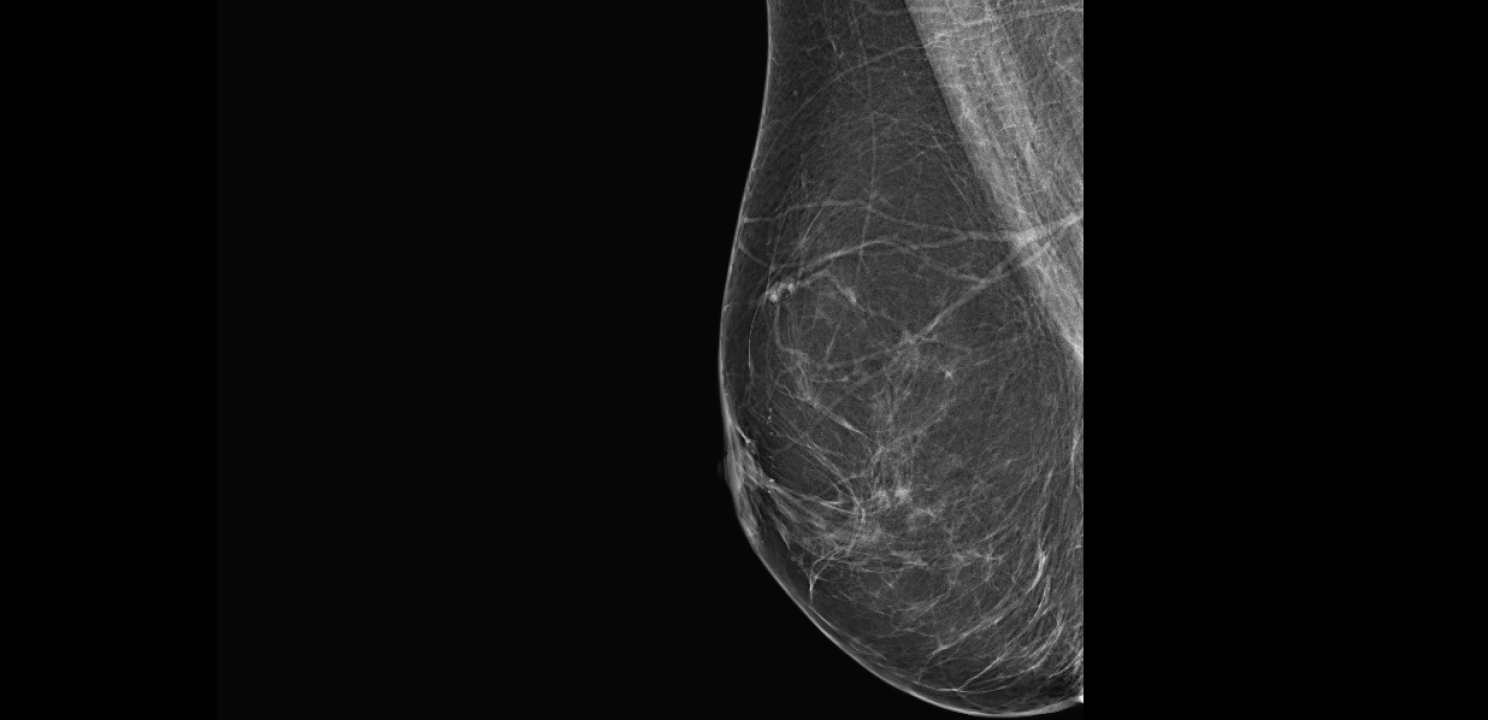

Zakažite preventivni pregled dojke u poliklinici Affidea Vita!

Listopad je mjesec borbe protiv raka dojke, najčešćeg raka od kojeg obolijeva jedna od deset žena u Hrvatskoj.